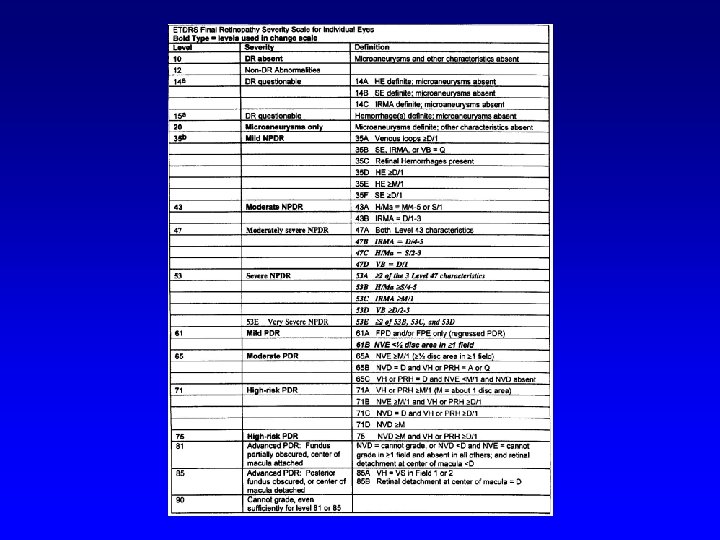

Classification of diabetic retinopathy 1. Nonproliferative DR (NPDR) 2. Proliferative DR (PDR) 3. Diabetic maculopathy (M) (each level of diabetic retinopathy may or may not beaccompanied by diabetic maculopathy)

Nonproliferative DR (NPDR) • • • Beginning Intermediate Advanced

Beginning NPDR

Intermediate NPDR

Intermediate NPDR

Advanced NPDR

Proliferative DR (PDR) • • • Light Intermediate Fully advanced VH- vitreous hemorrhage, PRHpreretinal hemorhage, TRD- retinal detachment at center of macula

Light PDR

Intermediate PDR

Fully advanced PDR

Fully advanced PDR

Vitreous hemorrhage in fully advanced PDR